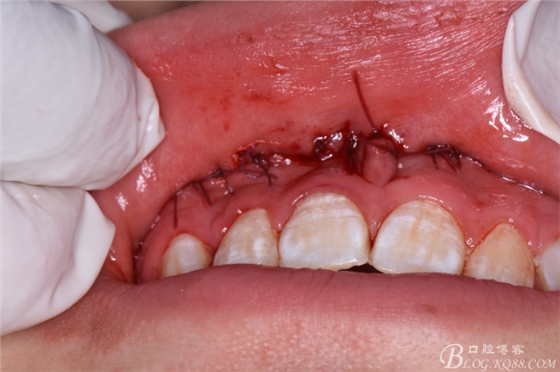

圖25.拔除后??p合完成的雙切口。